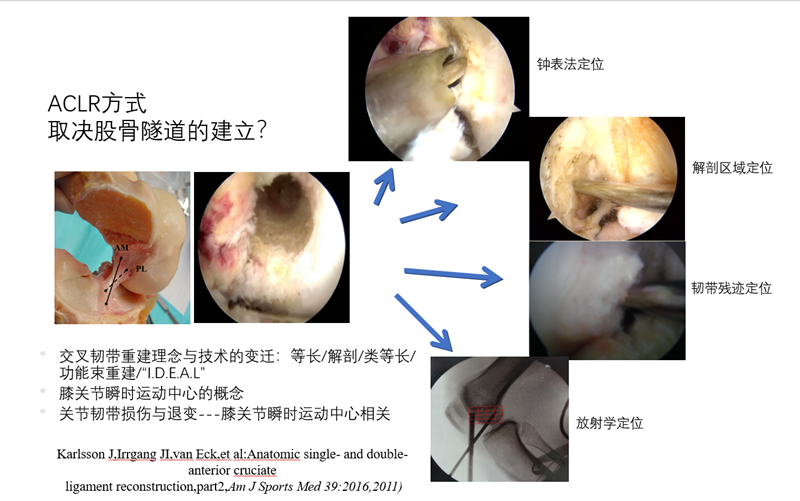

交叉韧带重建理念与技术的变迁:等长-解剖-类等长-功能束重建-“I.D.E.A.L”。三位外科医生在ACL重建领域加起来拥有70年的临床和研究经验。作为一个团队,他们对大量ACL重建解剖学,组织学,生物力学和临床数据进行了全面研究,并推荐使用首字母缩略词“I.D.E.A.L”作为描述完成股骨隧道指南的缩写术语。

ACL保残重建,以韧带残余为ACL-R的位点的重要参考,贯彻“I.D.E.A.L”理念。